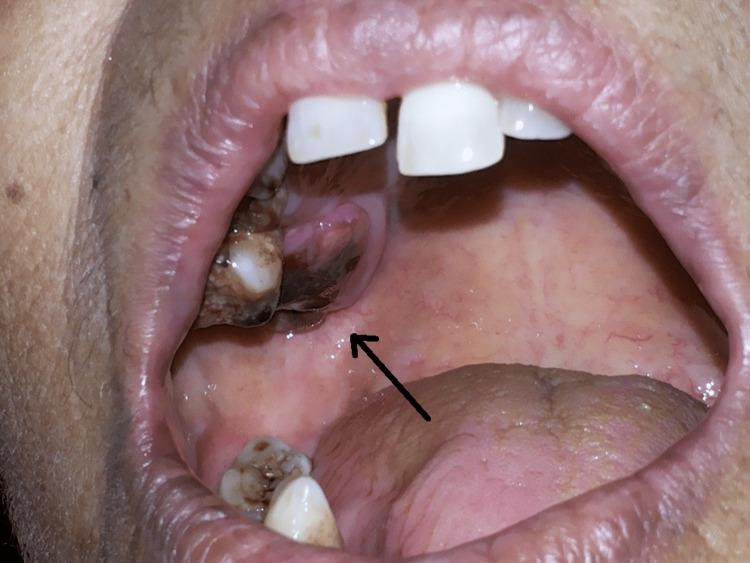

Melanoma of the oral cavity is a rare malignant tumor that develops from a malignant melanocytic or de novo from melanocytes within the normal mucosa or skin and appears blue, black, or reddish-brown. Oral mucosal melanoma has a higher proclivity for metastasis and attacks tissue more aggressively than any other malignant tumor in the mouth. Intestinal melanoma of the head and neck is an uncommon type of cancer that should be counted among the deadliest. Malignant melanoma of the oral cavity accounts for only 0.2%-8.0% of all reported melanoma, although accounting for 1.3% of all malignancies. Because most melanotic mucosal lesions are painless at first, the diagnosis is sometimes delayed until the ulcer or growth causes symptoms. Early detection is critical for effective therapy and the only way to improve survival and prognosis in patients with oral malignant melanoma due to its poor prognosis. To avoid oral melanomas, every single colored lesion identified in the oral cavity should be treated with suspicion and adequate inquiry because a colored lesion might expand, and it should be referred for a biopsy to avoid poisoning. This article shows how the oral clinic is important in the diagnosis of oral ulcers and argues that early detection is necessary to enhance patient outcomes.

口腔黑色素瘤是一种罕见的恶性肿瘤,它由恶性黑素细胞发展而来,或者起源于正常黏膜或皮肤内的黑素细胞,表现为蓝色、黑色或红棕色。口腔黏膜黑色素瘤比口腔内的任何其他恶性肿瘤更易发生转移,侵袭组织的能力更强。头颈部肠道黑色素瘤是一种罕见的癌症类型,属于最致命的癌症之一。口腔恶性黑色素瘤仅占所有报告黑色素瘤的0.2%-8.0%,尽管占所有恶性肿瘤的1.3%。由于大多数黑色素性黏膜病变起初无痛,诊断有时会延迟,直到溃疡或肿物引起症状。早期检测对于有效治疗至关重要,由于口腔恶性黑色素瘤预后较差,这也是改善患者生存和预后的唯一途径。为避免口腔黑色素瘤,口腔内发现的每一个有色病变都应受到怀疑并进行充分询问,因为有色病变可能会扩大,应转诊进行活检以避免误诊。本文展示了口腔诊所在口腔溃疡诊断中的重要性,并认为早期检测对于改善患者预后是必要的。